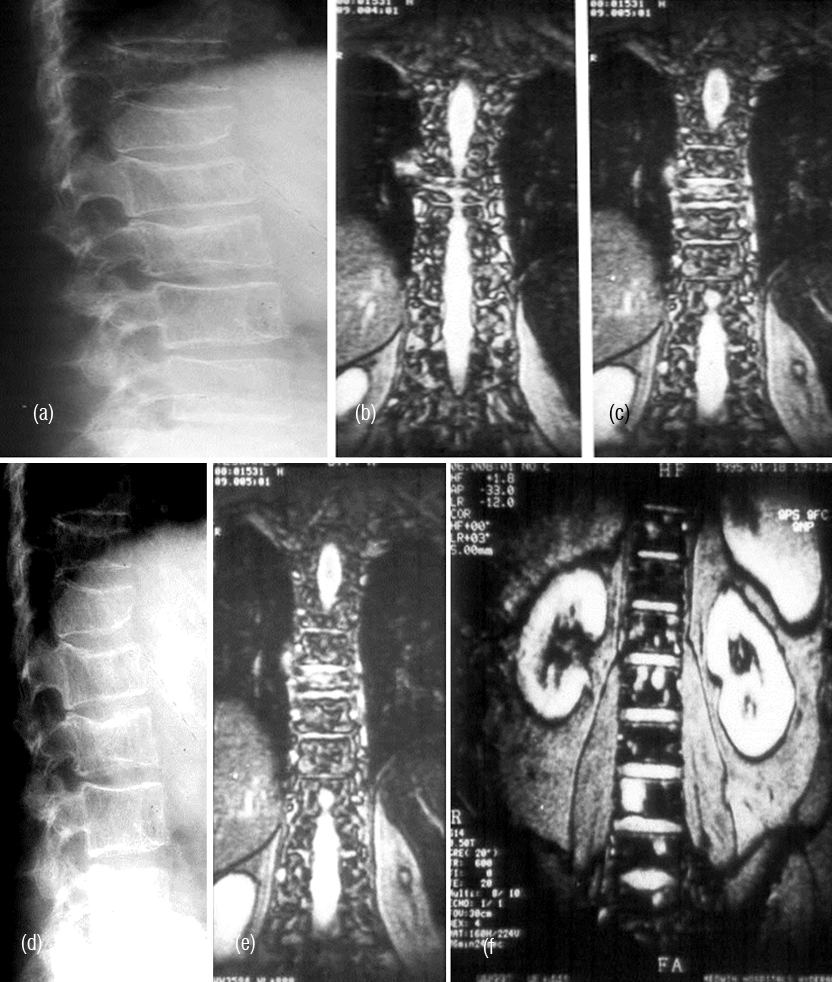

It radiologically shows a spectrum of manifestations. The bones particularly, in axial skeleton may present with multiple compression fractures. In 10-15% of cases, classical punched out lesions of the skull may be noted. In long tubular bones, pathological fractures are common with associated soft tissue swelling. In early skeletal lesions, moth eaten type of appearance is observed without any periosteal reaction (Figure 6ab). MRI is more sensitive to depict bone marrow lesions, whereas radionuclide scintigraphy with technetium 99 compounds is not that sensitive (Figure 7abcdef). The radiological appearances are listed in Table 3.

Figure 6: Multiple Myeloma – (a) Diffuse osteopenia with loss of trabeculae, (b) lytic lesions in the bodies.

Figure 7: (a,b,c) Multiple myeloma with osteopenia and early collapse of vertebral bodies BC MRI of the same patient. (d) plain films, (e, f) MRI.